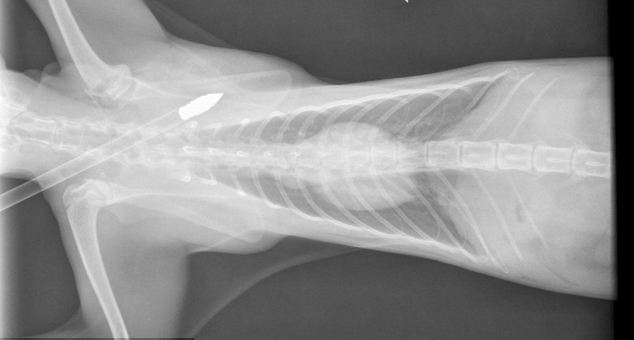

Το βέλος καρφώθηκε στο Gizmo περνώντας ξυστά από το κεφάλι και το στήθος του.

Ο ηλικίας ενός έτους γκρι γάτος της Nicola και του Graham Congrave από το Worcestershire τελικά χρειάστηκε μόνο δύο ράμματα, παρότι οι έντρομοι ιδιοκτήτες του τον βρήκαν να νιαουρίζει απελπισμένος μέσα σε μια λίμνη αίματος.